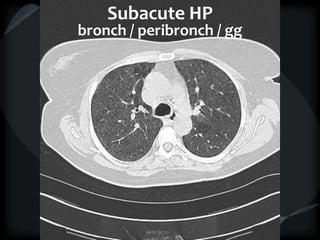

Subacute HP

bronch / peribronch / gg

BRONCHIOLAR

 Centrilobular nodules: small airways of secondary lobule

 1-3mm away from pleura

 Not sub pleural

 Not on fissures or septae

Primary bronchiolar disease Mixed bronchiolar

Tree-in-bud ground glass nodules+/-tree-in-bud

MAI, MTB sub acute HP